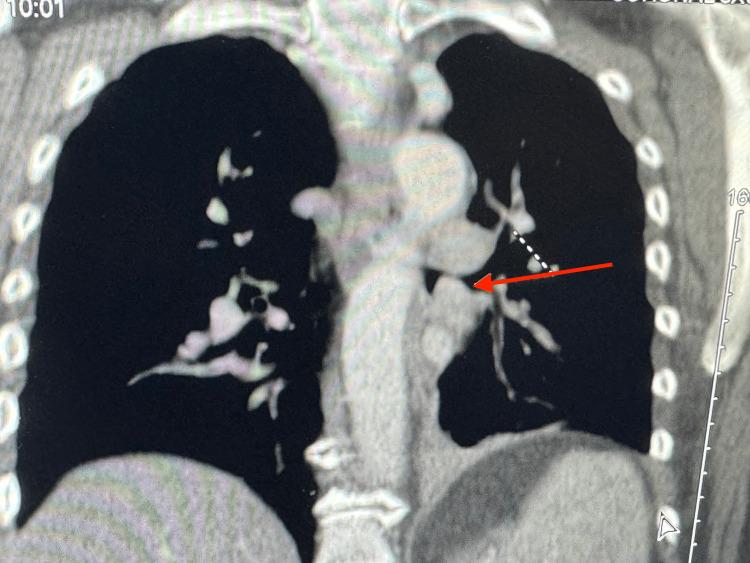

Endobronchial carcinoid tumors, a subset of neuroendocrine tumors, represent a rare but significant entity within pulmonary neoplasms, constituting less than 2% of all lung cancers. Our case report details the clinical presentation, diagnosis, and management of a 56-year-old female patient who presented with intermittent wheezing, mucoid cough, and recurrent pneumonia. Initial imaging and bronchoscopy identified an obstructive mass in the left lower bronchus. Histopathological examination of the bronchoscopic biopsy confirmed the diagnosis of a typical endobronchial carcinoid tumor. The patient underwent a successful left lower lobe lobectomy of the lung through left thoracotomy with regional and mediastinal lymph node dissection. Follow-up evaluations demonstrated no recurrence post-treatment. This case highlights the clinical features, diagnostic challenges, and therapeutic strategies associated with endobronchial carcinoid tumors, emphasizing the efficacy of a multidisciplinary approach in achieving favorable outcomes.